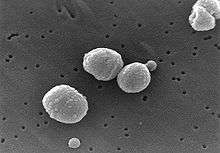

Bacteria

Bacteria are the most common cause of community-acquired pneumonia (CAP), with Streptococcus pneumoniae isolated in nearly 50% of cases.[29][30] Other commonly isolated bacteria include Haemophilus influenzae in 20%, Chlamydophila pneumoniae in 13%, and Mycoplasma pneumoniae in 3% of cases;[29] Staphylococcus aureus; Moraxella catarrhalis; Legionella pneumophila and Gram-negative bacilli.[16] A number of drug-resistant versions of the above infections are becoming more common, including drug-resistant Streptococcus pneumoniae (DRSP) and methicillin-resistant Staphylococcus aureus (MRSA).[20]

The spreading of organisms is facilitated when risk factors are present.[16] Alcoholism is associated with Streptococcus pneumoniae, anaerobic organisms, and Mycobacterium tuberculosis; smoking facilitates the effects of Streptococcus pneumoniae, Haemophilus influenzae, Moraxella catarrhalis, and Legionella pneumophila. Exposure to birds is associated with Chlamydia psittaci; farm animals with Coxiella burnetti; aspiration of stomach contents with anaerobic organisms; and cystic fibrosis with Pseudomonas aeruginosa and Staphylococcus aureus.[16] Streptococcus pneumoniae is more common in the winter,[16] and should be suspected in persons aspirating a large amount anaerobic organisms.[20]

Most bacteria enter the lungs via small aspirations of organisms residing in the throat or nose.[20] Half of normal people have these small aspirations during sleep.[24] While the throat always contains bacteria, potentially infectious ones reside there only at certain times and under certain conditions.[24] A minority of types of bacteria such as Mycobacterium tuberculosis and Legionella pneumophila reach the lungs via contaminated airborne droplets.[20] Bacteria can spread also via the blood.[21] Once in the lungs, bacteria may invade the spaces between cells and between alveoli, where the macrophages and neutrophils (defensive white blood cells) attempt to inactivate the bacteria.[42] The neutrophils also release cytokines, causing a general activation of the immune system.[43] This leads to the fever, chills, and fatigue common in bacterial pneumonia.[43] The neutrophils, bacteria, and fluid from surrounding blood vessels fill the alveoli, resulting in the consolidation seen on chest X-ray.[44]

Edwin Klebs was the first to observe bacteria in the airways of persons having died of pneumonia in 1875.[102] Initial work identifying the two common bacterial causes, Streptococcus pneumoniae and Klebsiella pneumoniae, was performed by Carl Friedländer[103] and Albert Fränkel[104] in 1882 and 1884, respectively. Friedländer's initial work introduced the Gram stain, a fundamental laboratory test still used today to identify and categorize bacteria. Christian Gram's paper describing the procedure in 1884 helped to differentiate the two bacteria, and showed that pneumonia could be caused by more than one microorganism.[105]